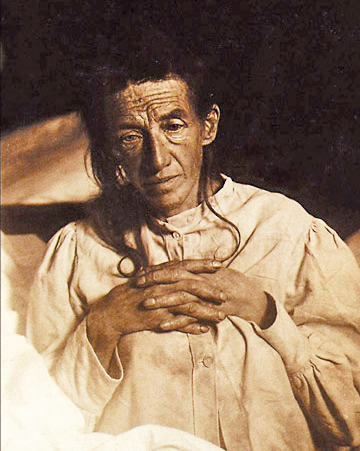

Помимо этого признаками болезни являются невозможность приготовления еды, планирования расписания, неспособность выполнять принятые решения, тем более, если они требуют множественной последовательности действий. Сюда также попадают резкие и беспричинные изменения в настроении, неожиданное возбуждение, добровольная социальная изоляция и даже изменение походки.

Это по-разному. Некоторые люди испытывают состояние умеренного когнитивного нарушения. Например, провалы в памяти или падение уровня квалификации при принятии решений. Но помехи такого рода не влияют на независимость человека. И болезнь Альцгеймера вовсе не обязательна в таких случаях. Ну, постарел, говорят окружающие. Что делать! Возраст берет свое.

Совсем недавно ученые начали распознавать даже более ранние стадии развития болезни: субъективное снижение когнитивных функций. Такие люди сами замечают проколы в их памяти или размышлениях. Конечно, это тревожит, даже если окружающие и не замечают провалов. Специалисты обнаружили, что порой люди распознают эту проблему перед тем, как они заболевают по-настоящему. И вот когда это случается, то можно точно сказать, что вероятность возникновения болезни Альцгеймера растет.

Болезнь обычно разделяется на три стадии: мягкая, умеренная и серьезная. Первые две могут длиться годами, и зачастую нет никакой возможности предсказать темп развития недуга.